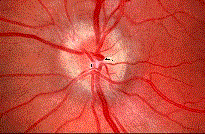

问题 患者,女性70岁,因双眼视力骤降半天就诊。检查:右眼视力0.02,左眼0.03,结膜无充血,角膜透明,角膜后沉着物阴性,瞳孔对光反射对称、迟钝,晶状体轻度混浊,玻璃体无混浊;视乳头充血水肿。 (如图)请问首选需行哪种检查 ( )

选项 A、CT B、验光 C、眼底荧光造影 D、视野检查 E、VEP

答案 D